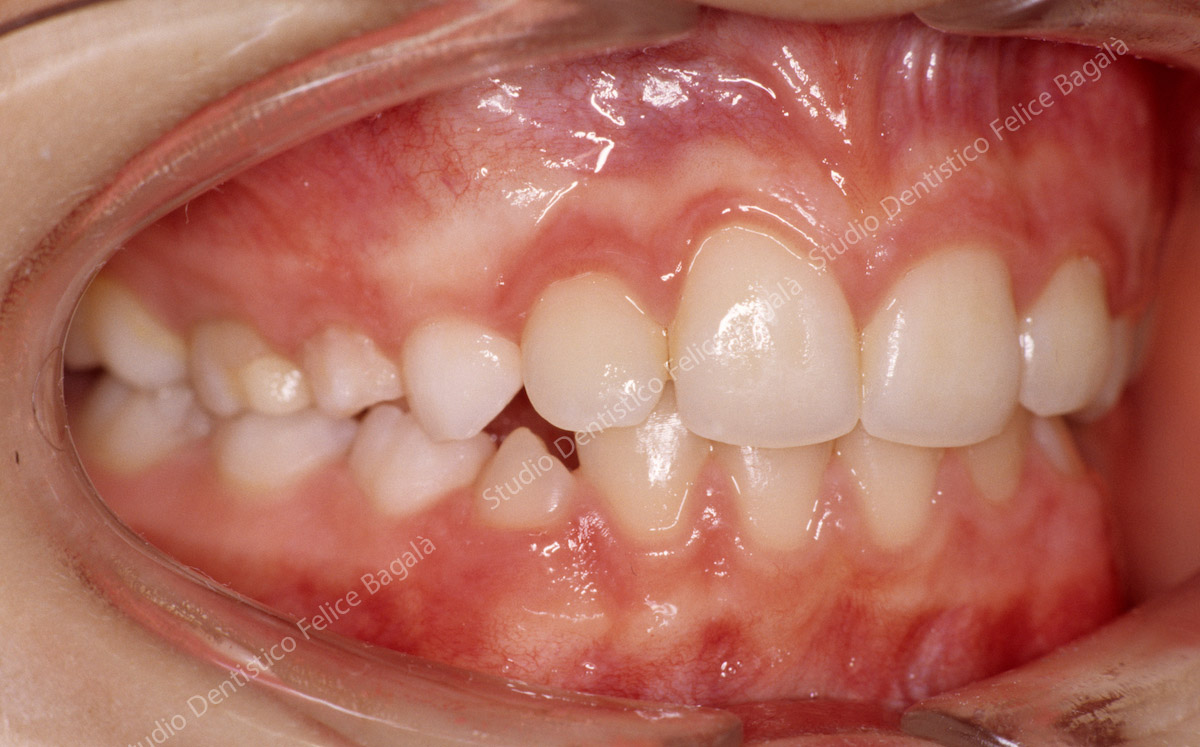

IL CASO DI DANIELE (MORSO CROCIATO)

Daniele 8 anni Morso crociato destro con deviazione mandibolare  e linee mediane dallo stesso lato (vedi frecce nere). Dopo allargamento della parte superiore (mascellare e palato) la mandibola si porta al centro (vedi frecce nere) . Daniele da quel momento continuerà a crescere e sarà controllato periodicamente. Dopo questo breve fase intercettiva di durata di 8/10 mesi non ha avuto più alcun bisogno di ortodonzia. Le deviazioni mandibolari da morso crociato vengono annoverate tra i principali motivi di disturbi muscolo articolari ( Disfunzioni ATM) nell’adulto.

Dopo